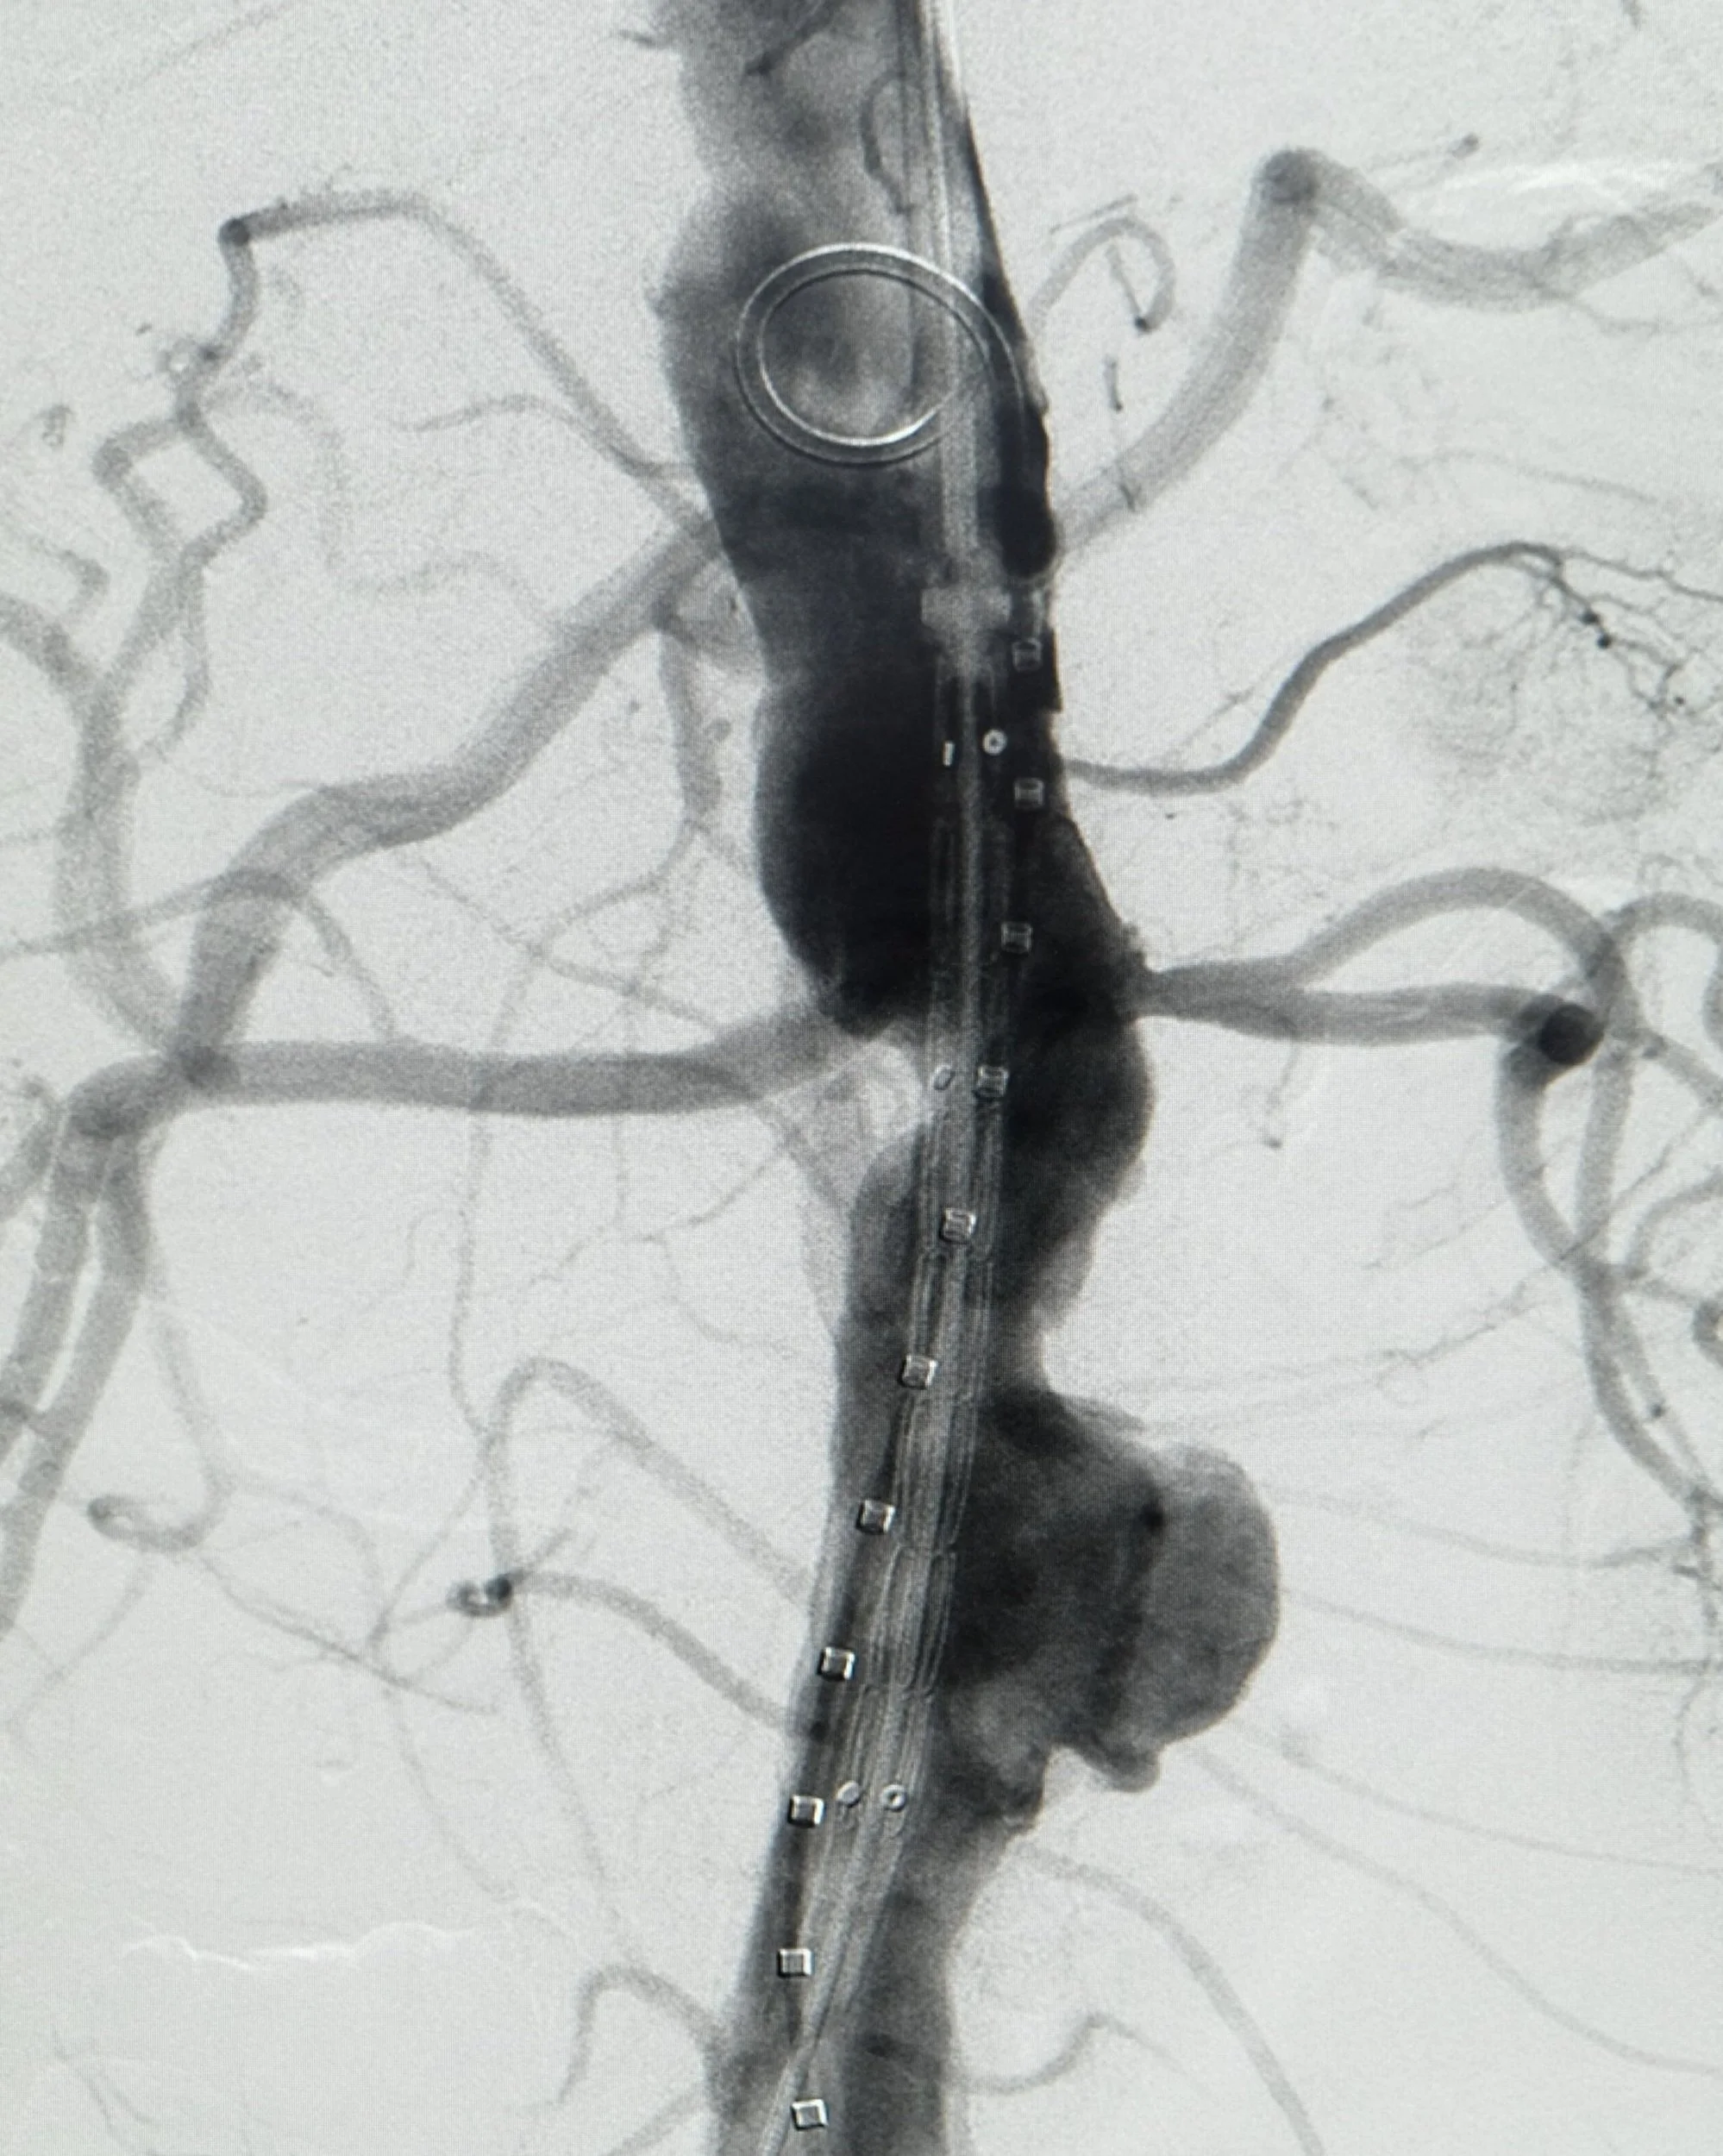

Endovascular stent graft visualised within thoraco-abdominal aorta.

Positioning: Thoraco-abdominal endovacular device